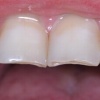

Diasteem

Diasteem – vahe esimeste hammaste vahel. Esineb 50%-l 6-8 aastastel lastel. Kuni 2 mm diasteemi puhul on, peale lateraalse intsisiivi ja silmahamba lõikumist, võimalik diasteemi iseeneslik sulgumine. Diasteem, mille suurus...